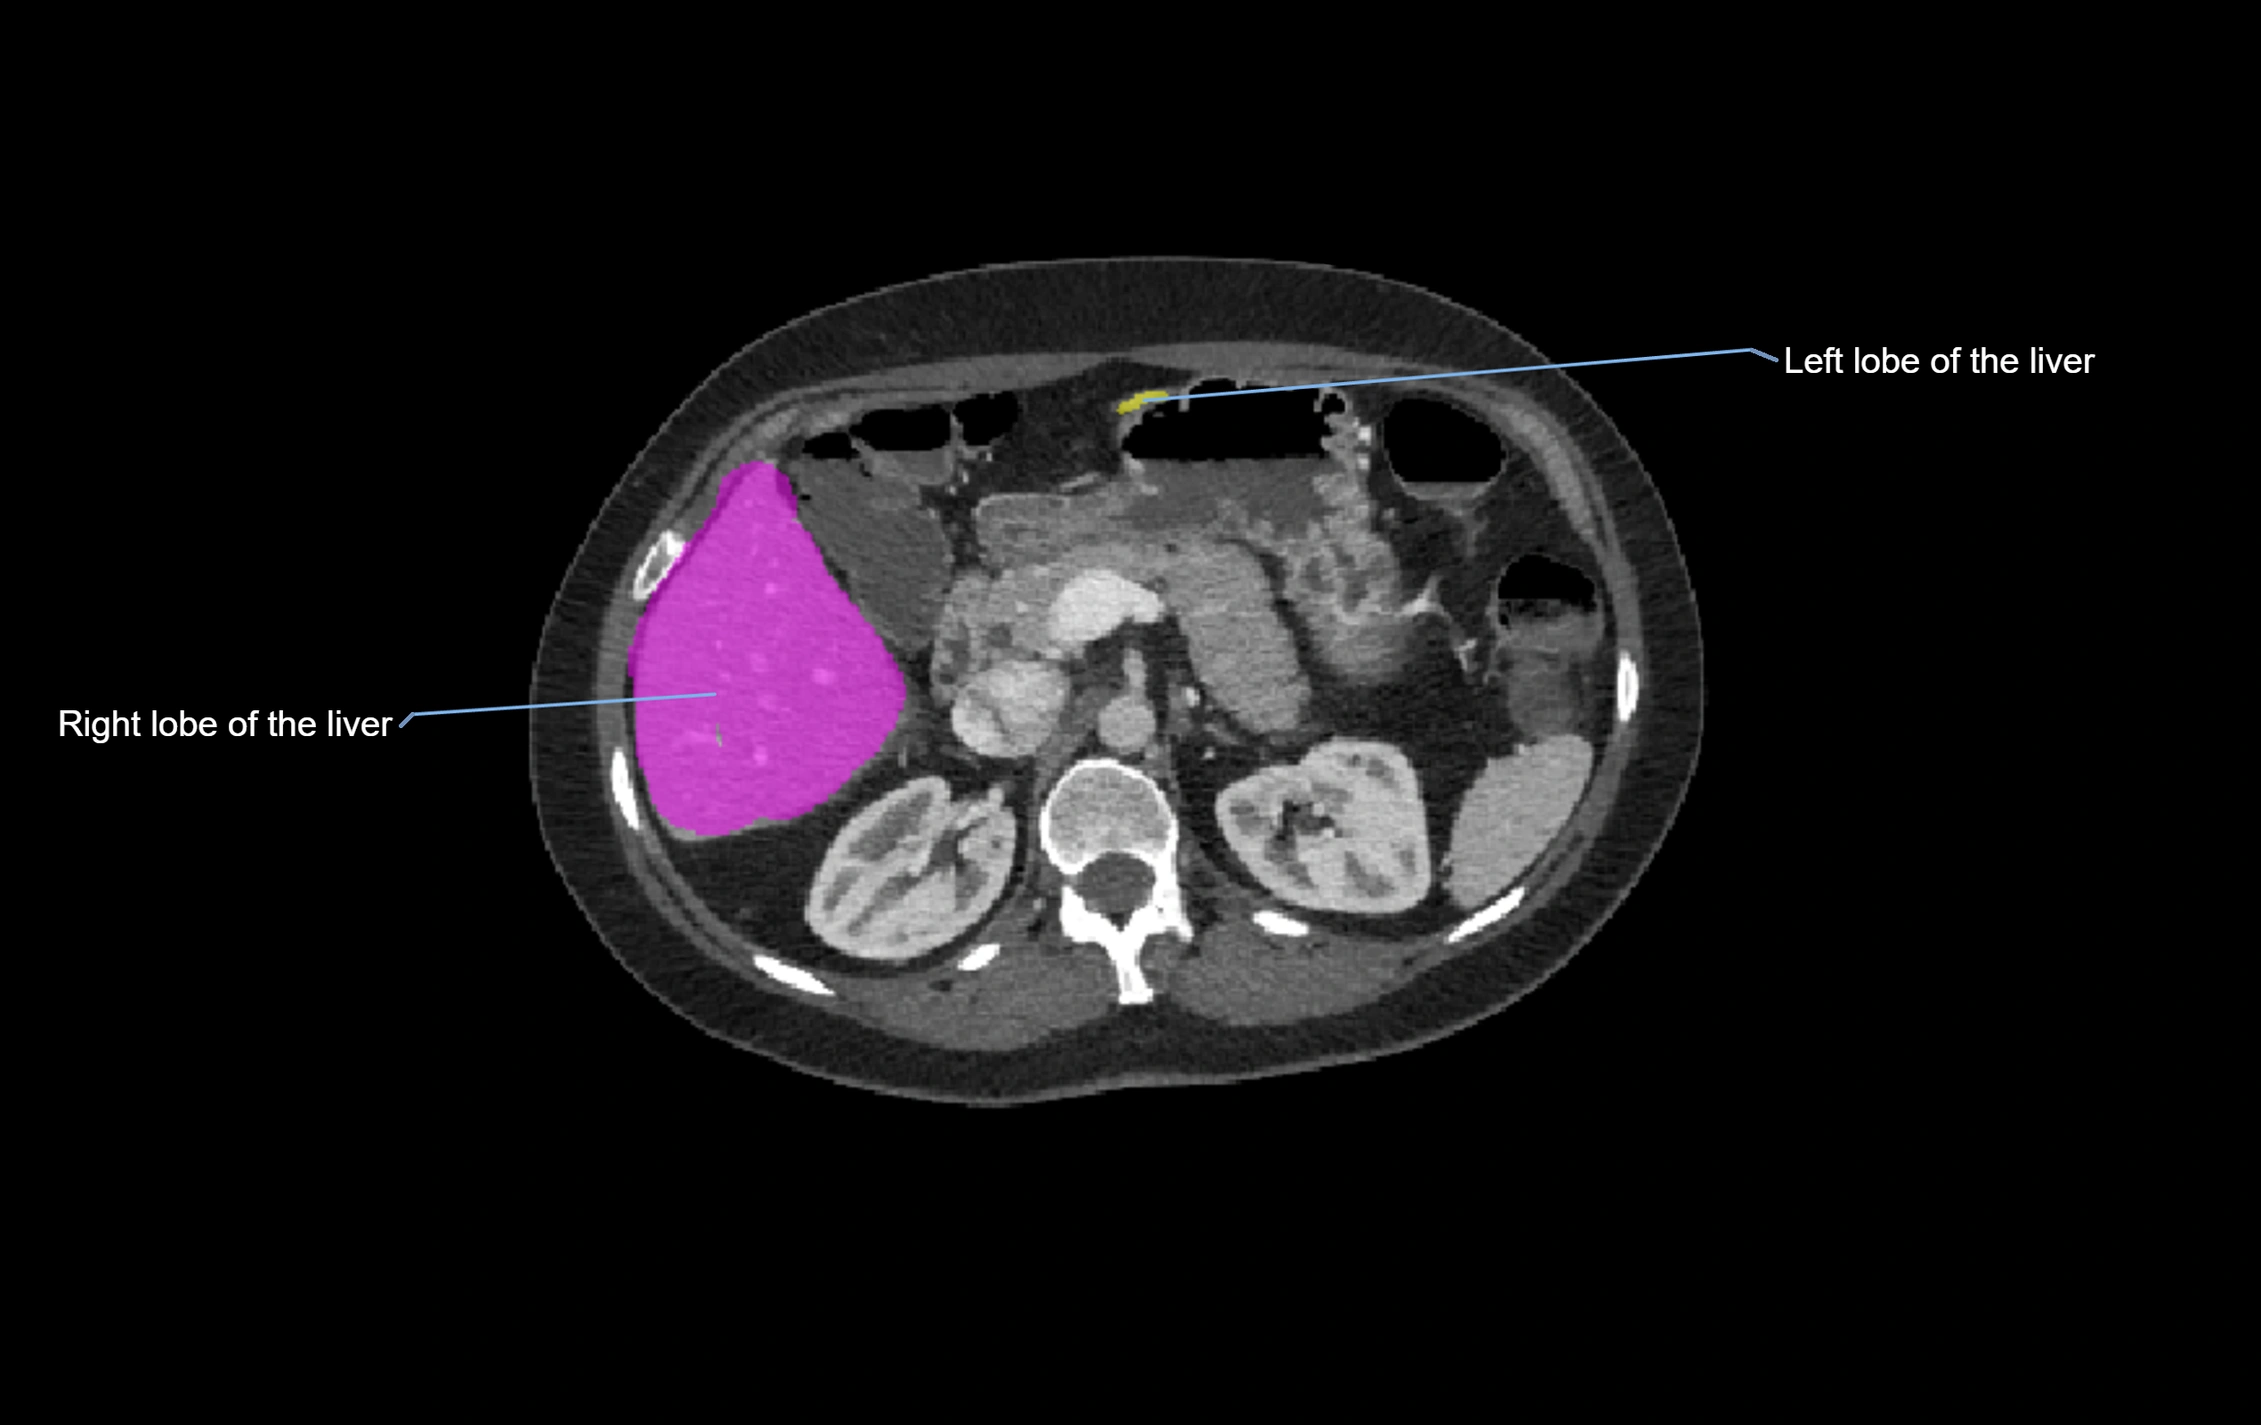

CT Appearance

CT Pre-Contrast:

• Caudate lobe appears as a soft-tissue density, isodense to the rest of the liver

• Enlargement may be appreciated in cirrhosis or Budd–Chiari syndrome

CT Post-Contrast:

• Homogeneous enhancement in the portal venous phase, similar to rest of liver

• Independent venous drainage into the IVC may be visualized

• Lesions follow characteristic CT enhancement patterns (HCC: arterial hyperenhancement with washout; hemangiomas: peripheral nodular enhancement with centripetal fill-in)

CT Image

image